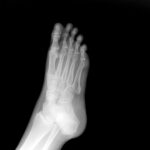

Ankle fractures are often the result of high energy trauma like what you might experience in a car accident or a collision in athletic activity, but as we get older, it oftentimes takes less force for these types of injuries to occur. A small slip or a fall from a few feet can lead to […]

Bone density, weight, age and activity level are all factors that impact a person’s likelihood of suffering a foot fracture. Researchers at the University of Pittsburgh recently attempted to decipher exactly which factors put women at the greatest risk of suffering certain fractures. What they found may surprise you. For their study, researchers surveyed nearly […]